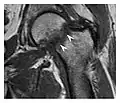

The greater tuberosity of the humerus is also an illustrative location of occult fractures. The osseous injury may follow seizures, glenohumeral dislocation, forced abduction, or direct impaction. They are commonly discovered on MRI in symptomatic patients with suspicion of rotator cuff tear. Coronal images are best suited for detection. They appear as crescentic oblique lines surrounded by a bone marrow edema pattern (Figure 5). The rotator cuff must be inspected since associated ligamentous lesions are common. In the ankle, malleoli and tarsal bones should be checked carefully for any cortical disruptions and radiolucent lines that may reveal a fracture. Awareness of the exact location of the pain will help direct the attention of the interpreter when searching for very subtle signs of fracture (Figure 6).[1]

a

b